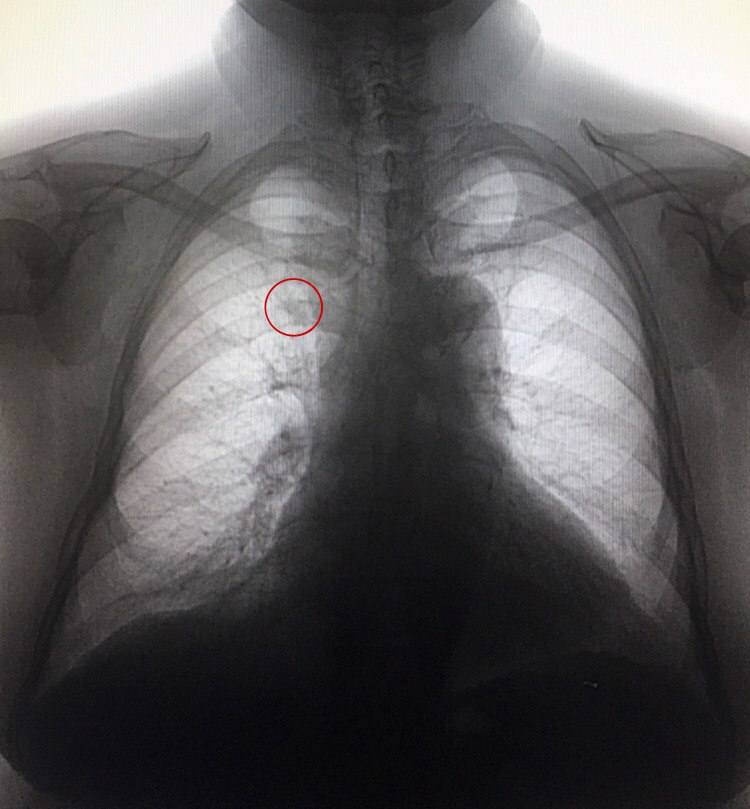

Подскажите пожалуйста то, что я в красный кружок обвела сосуды так получились или нет? Ж, 1946 года рождения, архива нет.

Остеоартроз грудинно-реберного

Плюс поворот